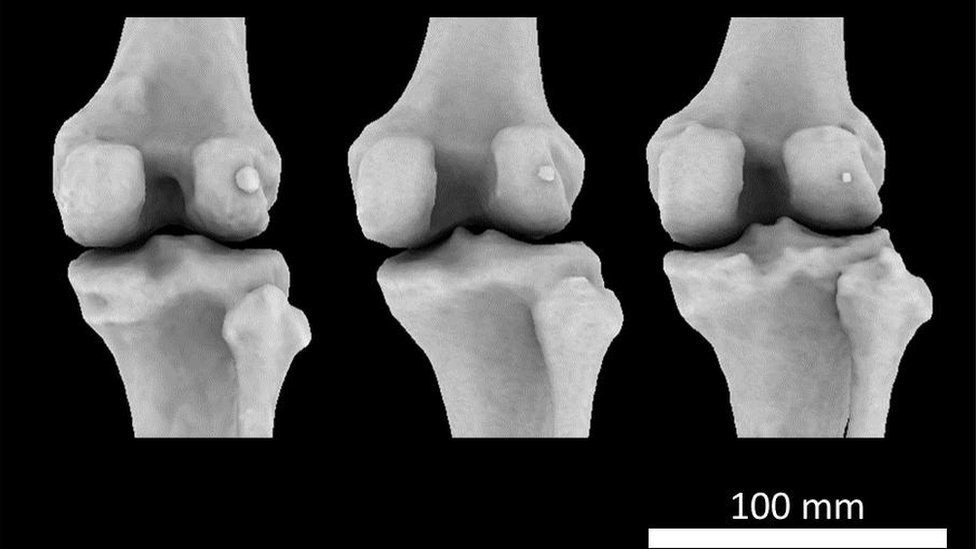

La flecha señala dónde se encuentra el hueso fabela. Crédito: Imperial College London